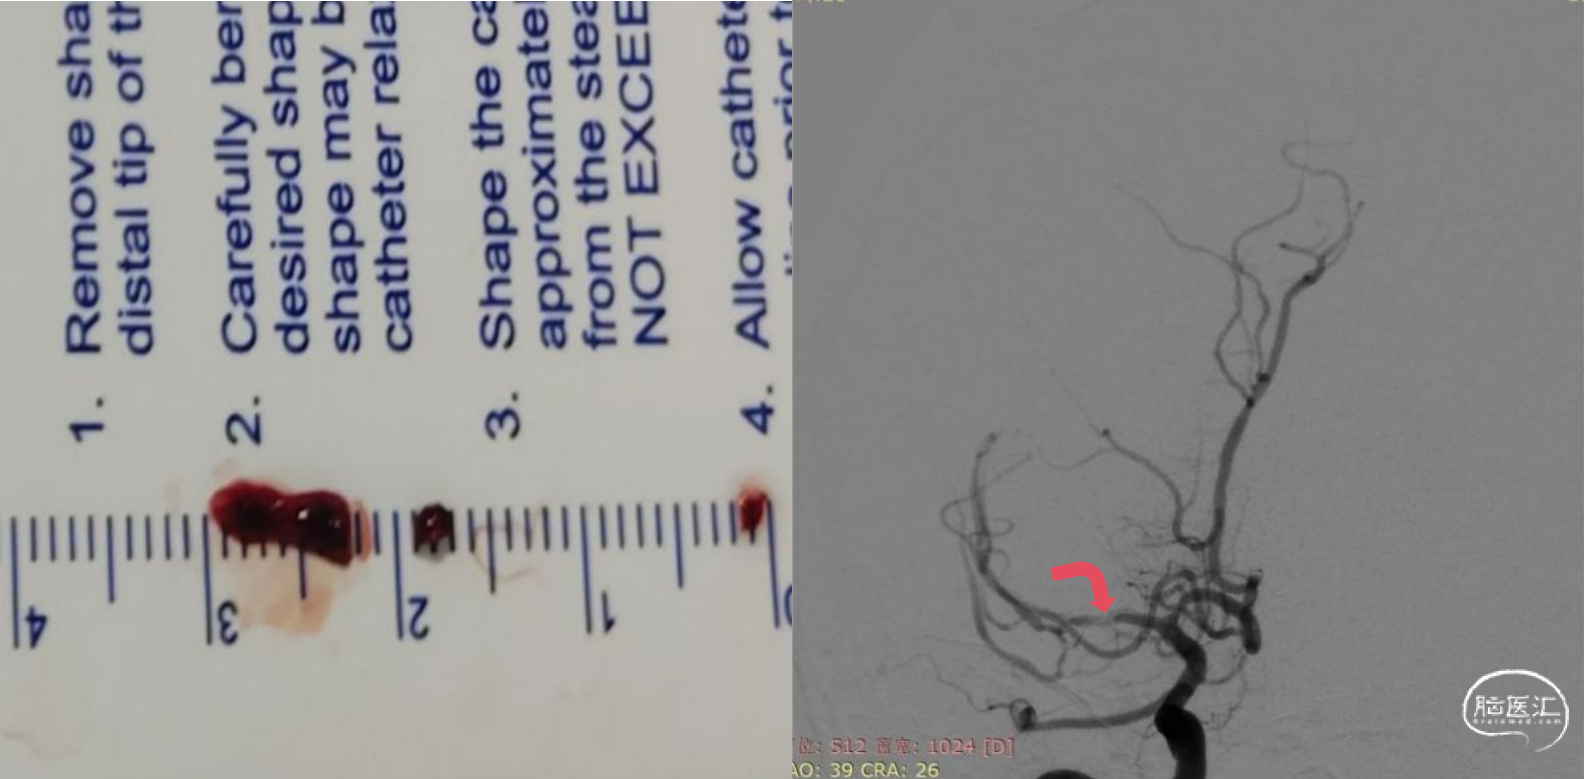

6F长鞘配合5F多功能导管,在泥鳅导丝引导下同轴技术选入右侧颈内动脉C2段,撤出导丝以及5F多功能导管,随后造影路图下将微导丝配合微导管送达右侧大脑中动脉上干M2段。6F血栓抽吸导管在微导丝配合微导管同轴引导下选入右侧大脑中动脉M1段起始,随后撤出微导丝和微导管,采用ADAPT技术持续负压抽吸,抽出一3.0mm*8.0mm暗红色血栓,再次造影提示右侧大脑中动脉复通,但可见右侧大脑中动脉M1段重度狭窄。

随后使用一次性球囊扩张导管(2.0mm*9.0mm),8个atm压力下缓慢扩张。扩张后即刻造影提示右侧大脑中动脉狭窄解除满意,前向血流eTICI3级。

观察20分钟,管腔无回缩,前向血流eTICI3级,遂结束手术。